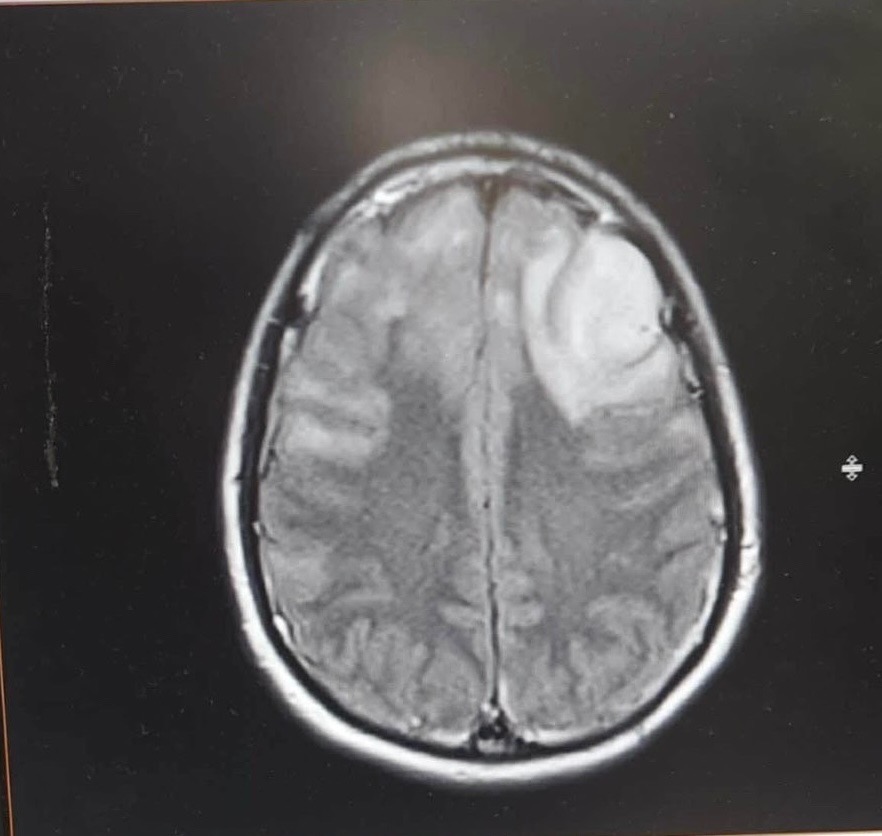

Instead of planning his future, Avery spends his days in pain and fear. He lives with frequent seizures, two tumors in his brain, and a broken back that makes even the simplest movements exhausting. His body doesn’t give him breaks, and neither does life.

There are moments when Avery is scared to fall asleep, afraid a seizure will come and no one will be there to help. The pain in his back never fully fades. The headaches remind him every day that the tumors are still there. This is not something anyone—especially someone so young—should have to endure.